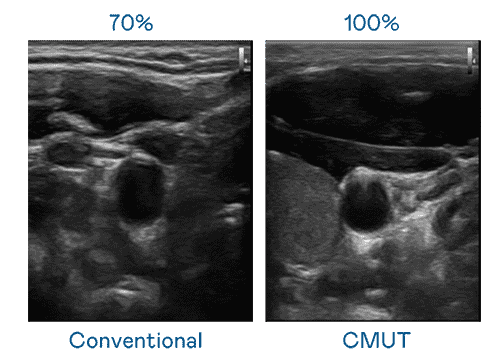

CMUT 技术是一种用电容式微机电元件来产生超音波讯号的技术。。与传统 PZT 压电式技术相比,,CMUT 频宽增加 30%,,更宽频的超音波讯号让影像解析度大幅提升,,,是实现高影像品质医疗超音波扫描、、、促进精准医疗发展的关键技术。。。。

大频宽带来超清晰影像

超音波影像的解析度高低,,,,首先取决于探头能发出的讯号频宽。。。赏金国际 CMUT 可提供高清晰的超音波讯号,,提供高频宽、、高灵敏度、、影像纹理细节更高的超音波影像,,协助医护人员缩短影像判读时间及利用精准的医疗影像进行诊断。。。